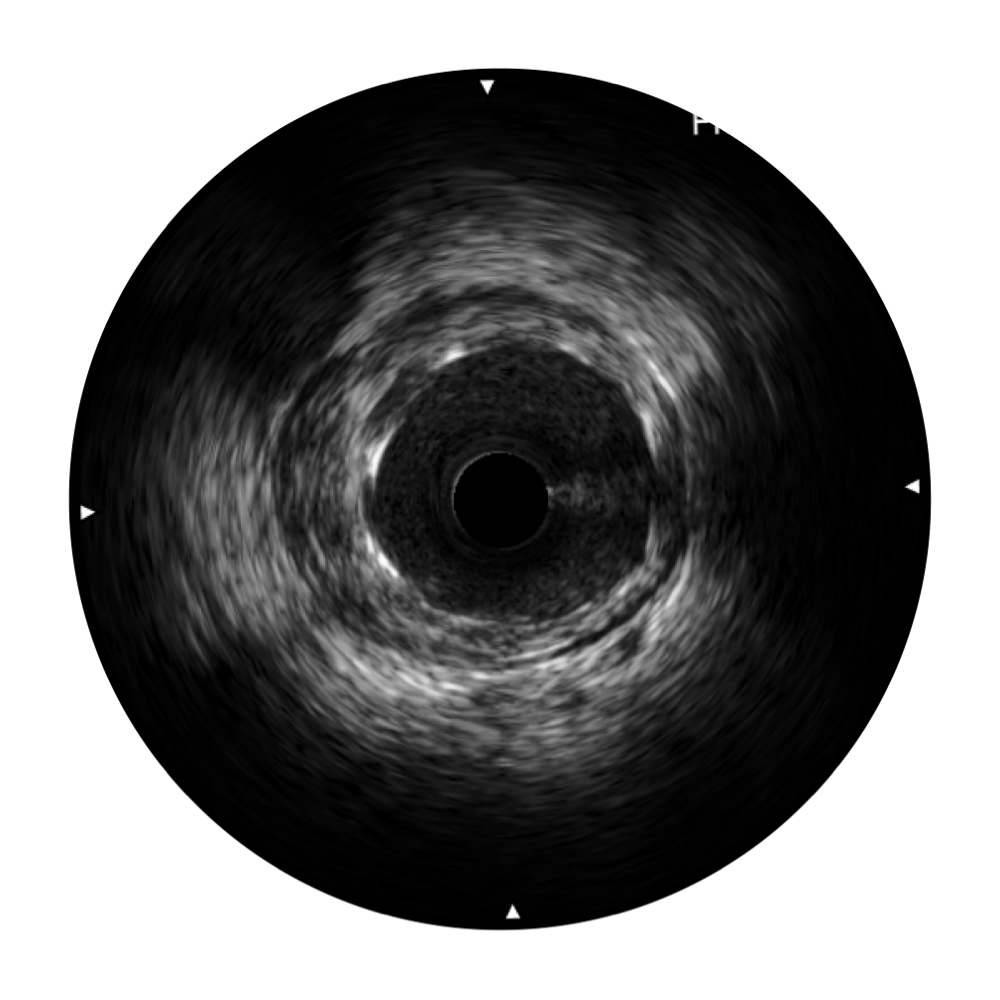

传统IVUS图像

对比传统IVUS导管成像,16877太阳集团宽频IVUS图像的近场支架梁显影更细腻,远场中膜外血管仍清晰可辨,兼顾远中近,兼顾分辨力与穿透深度